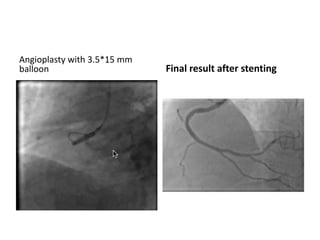

RCA ostium sub occlusion calcification +++

JR4 6F

Anchoring guide wire technique with BMW

in conus artery to stabilize guide catheter

Angioplasty with 3.5*15 mm

balloon Final result after stenting